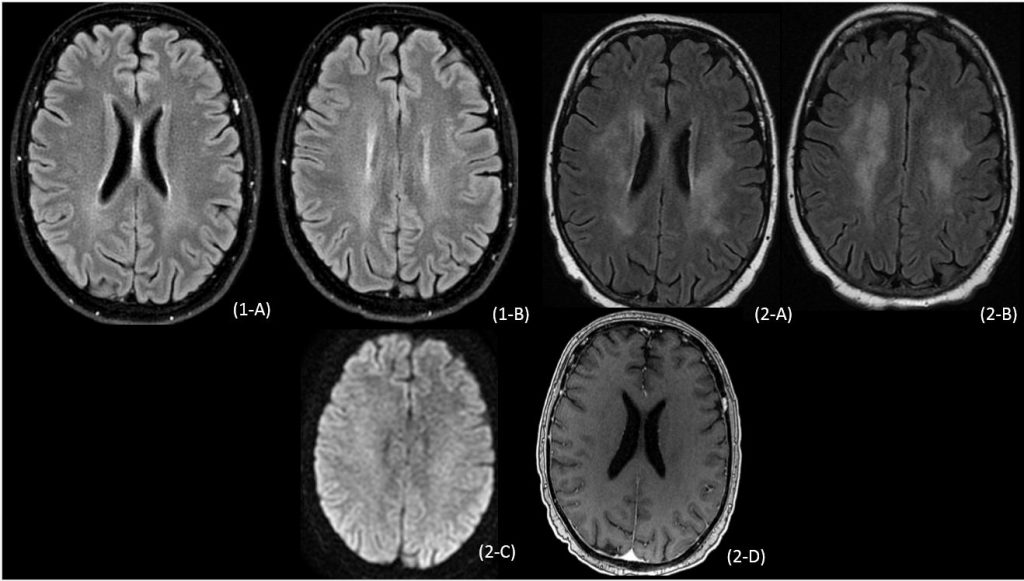

Figuras 1A y 1B RM realizada en noviembre 2018 empleando secuencias FLAIR plano axial. No se observan alteraciones significativas.

Figuras 2 (A-D). RM realizada en enero de 2019 empleando secuencias FLAIR, difusión y T1 con contraste en el plano axial. Lesiones hiperintensas confluentes en sustancia blanca periventricular y de centro semiovales, sin restricción en difusión ni captación patológica de contraste.